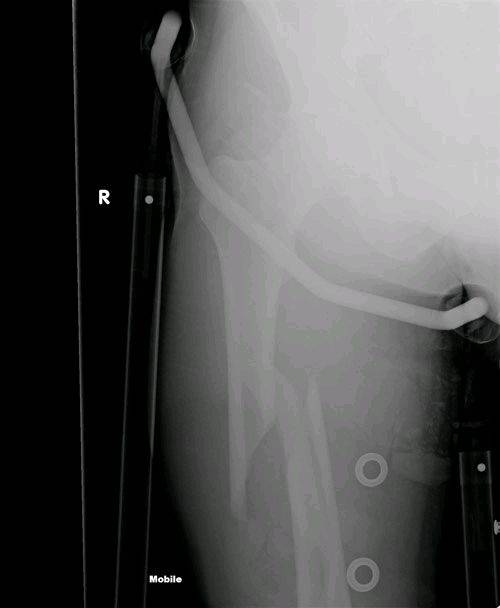

Kiteboarding Fractured femure